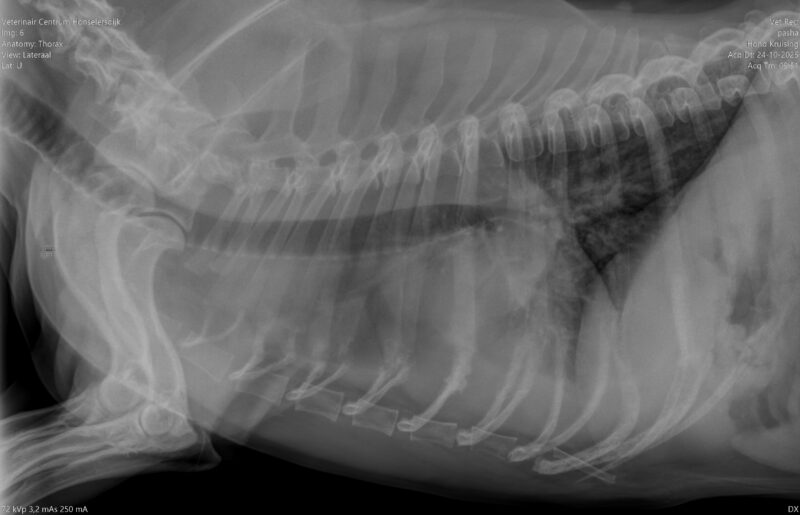

beoordeling RX thorax bij hoestende hond

Graag zou ik jullie hulp willen vragen over de volgende patient: Het is een kruising jack russel met franse bulldog van 15 jaar oud, Mk. Hij is 4 weken plots begonnen met hoesten. Het is een droge piepende hoest, dat vaak eindigt in even kokhalzen. Het hoesten is niet gekoppeld aan activiteit, maar in diepe slaap hoest hij niet. Eetlust…